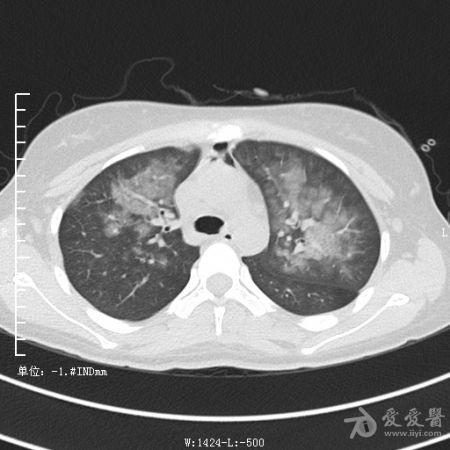

典型支气管扩张及肺水肿CT片

典型支气管扩张肺水肿